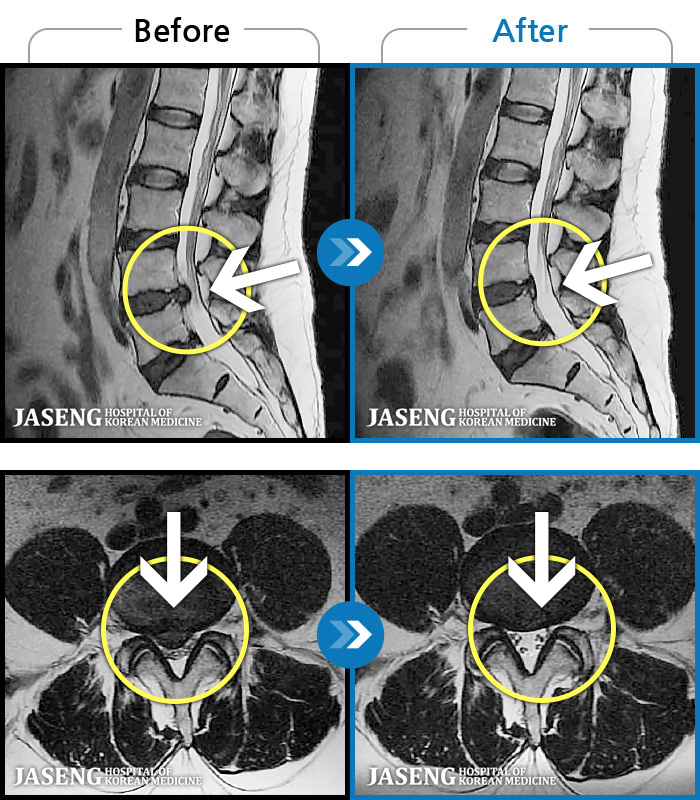

MRI ġ

1,237 MRI ũ ʸ Ȯϼ.

㸮 ϻ .